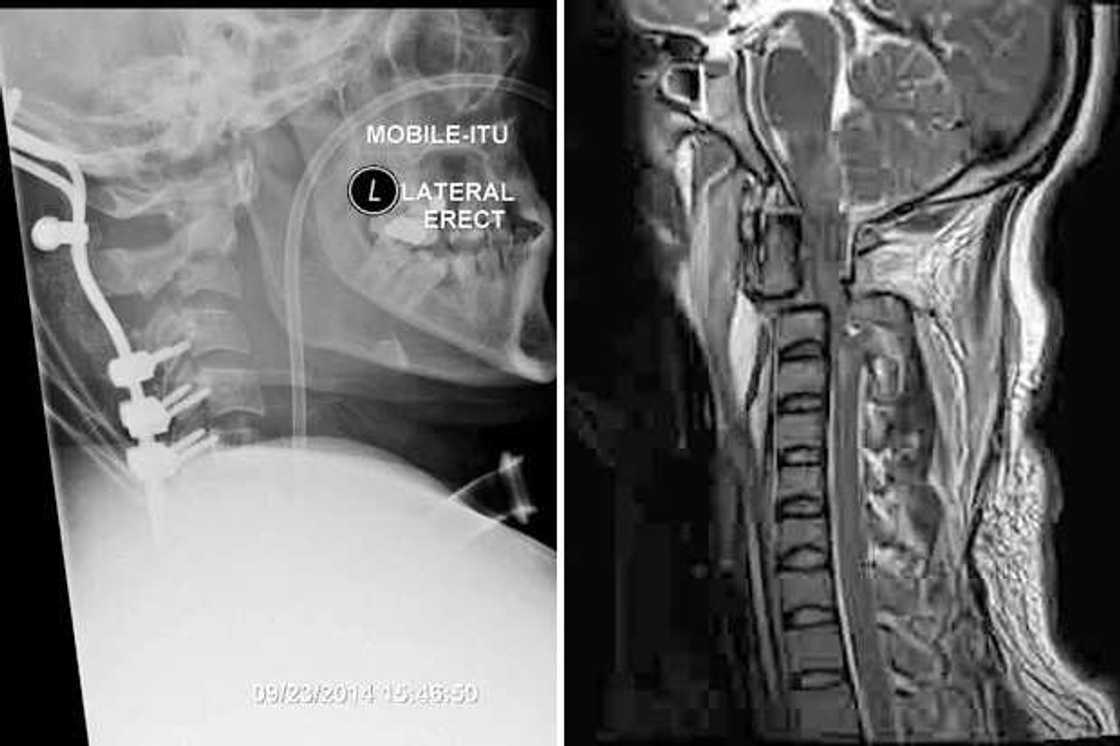

The medics managed to reattach his skull to his spine with a metal plate and bolts in an extremely rare operation but could not do anything with his paralysis. Despite his miraculous recovery it is highly unlikely he will ever be able to talk or walk again. Tony – who communicates him through an electric board – said: "I love Karen with all my heart and I can't wait to go home to get back to the life I had."